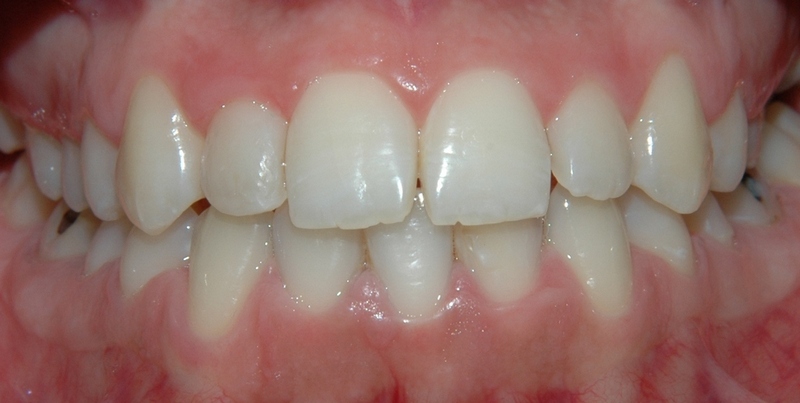

Dentalna protetika - krunice, mostovi, proteze

Vrhunska optička estetska i mehanička svojstva bezmetalnih keramičkih radova